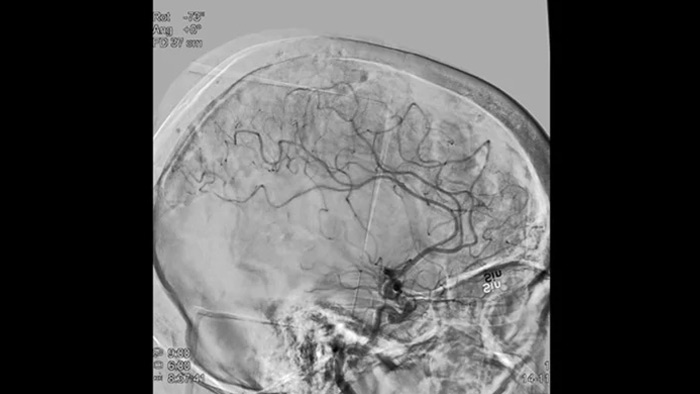

Imágenes nítidas con DSA 2D con tecnología ClarityIQ

Angiografía por sustracción digital (ASD) 2D con tecnología ClarityIQ

ClarityIQ aplica la compensación automática del movimiento durante la DSA en tiempo real para mantener imágenes nítidas de los vasos. Esto permite tomar decisiones con confianza durante los procedimientos para atender accidentes cerebrovasculares.

Confirmar el éxito del tratamiento

Visualización de la ASD

Las visualizaciones de la DSA de alta calidad le permiten evaluar si ha recuperado el coágulo completo y si los trozos de coágulo se han dispersado distalmente en el cerebro. Puede comprobar el restablecimiento del flujo sanguíneo en las áreas de penumbra y comprobar si hay hemorragias periprocedimiento.